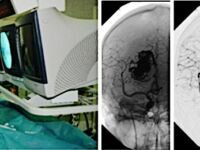

Виды медико-хирургической помощи